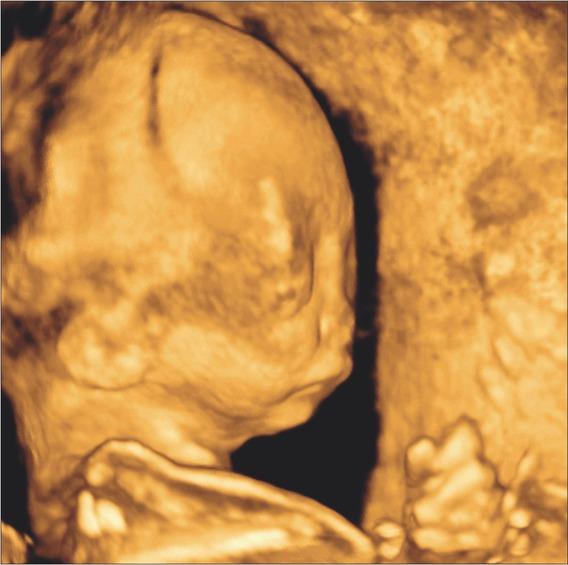

Case 2. The subsequent (third) pregnancy of the couple was uneventful during the first trimester. Ultrasound examination at 22 weeks of gestation, showed normal fetal growth, however, broad nasal bridge, micrognathia and low set ears were detected (Figures 1 and 2). Fetal fingers were also broadly spaced with abducted thumb and possible agenesis of some metacarpal bones. Spina bifida in a lumbosacral region was also present (Figure 3). Fetal magnetic resonance imaging (MRI) was performed, confirming mandibular and nasal hypoplasia, as well as lumbosacral dysraphism with meningocele. Karyotyping yielded a normal male result. The pregnancy was terminated at 24 weeks of gestation at the parents request. Postmortem autopsy confirmed facial dysmorphism, hypertelorism, downslanting palpebral fissures and micrognathia. The index finger on both hands was significantly longer than the other fingers.

Ultrasound image of case 2 showing micrognathia and low-set ears.

Ultrasound image of case 2 showing hypertelorism.